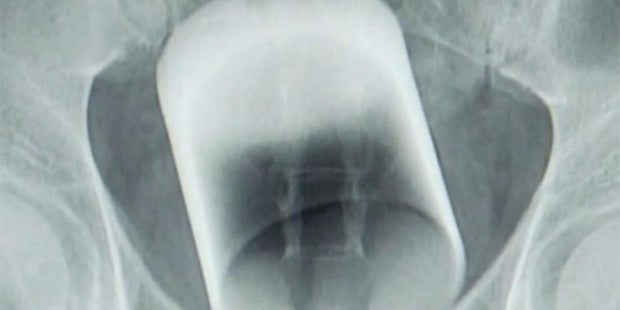

Die Ärzte konnten kaum glauben, was sie auf dem Röntgenbild sahen.

Ärzte in Guangzhou (China) staunten nicht schlecht, als sie das Röntgenbild eines Patienten zu Gesicht bekamen. Denn im Enddarm des Mannes steckte ein ganzes Trinkglas - ein Glas mit einem Durchmesser von acht Zentimetern und sieben Zentimetern Höhe.

Die Ärzte konnten das Glas entfernen, ohne es zu zerbrechen. Eine medizinische Meisterleistung, denn der Schließmuskel übte so viel Druck auf das Glas aus, dass es beinahe zerbrochen wäre. Die Scherben hätten dann zum Tod des Patienten führen können, so "The Shanghailist".